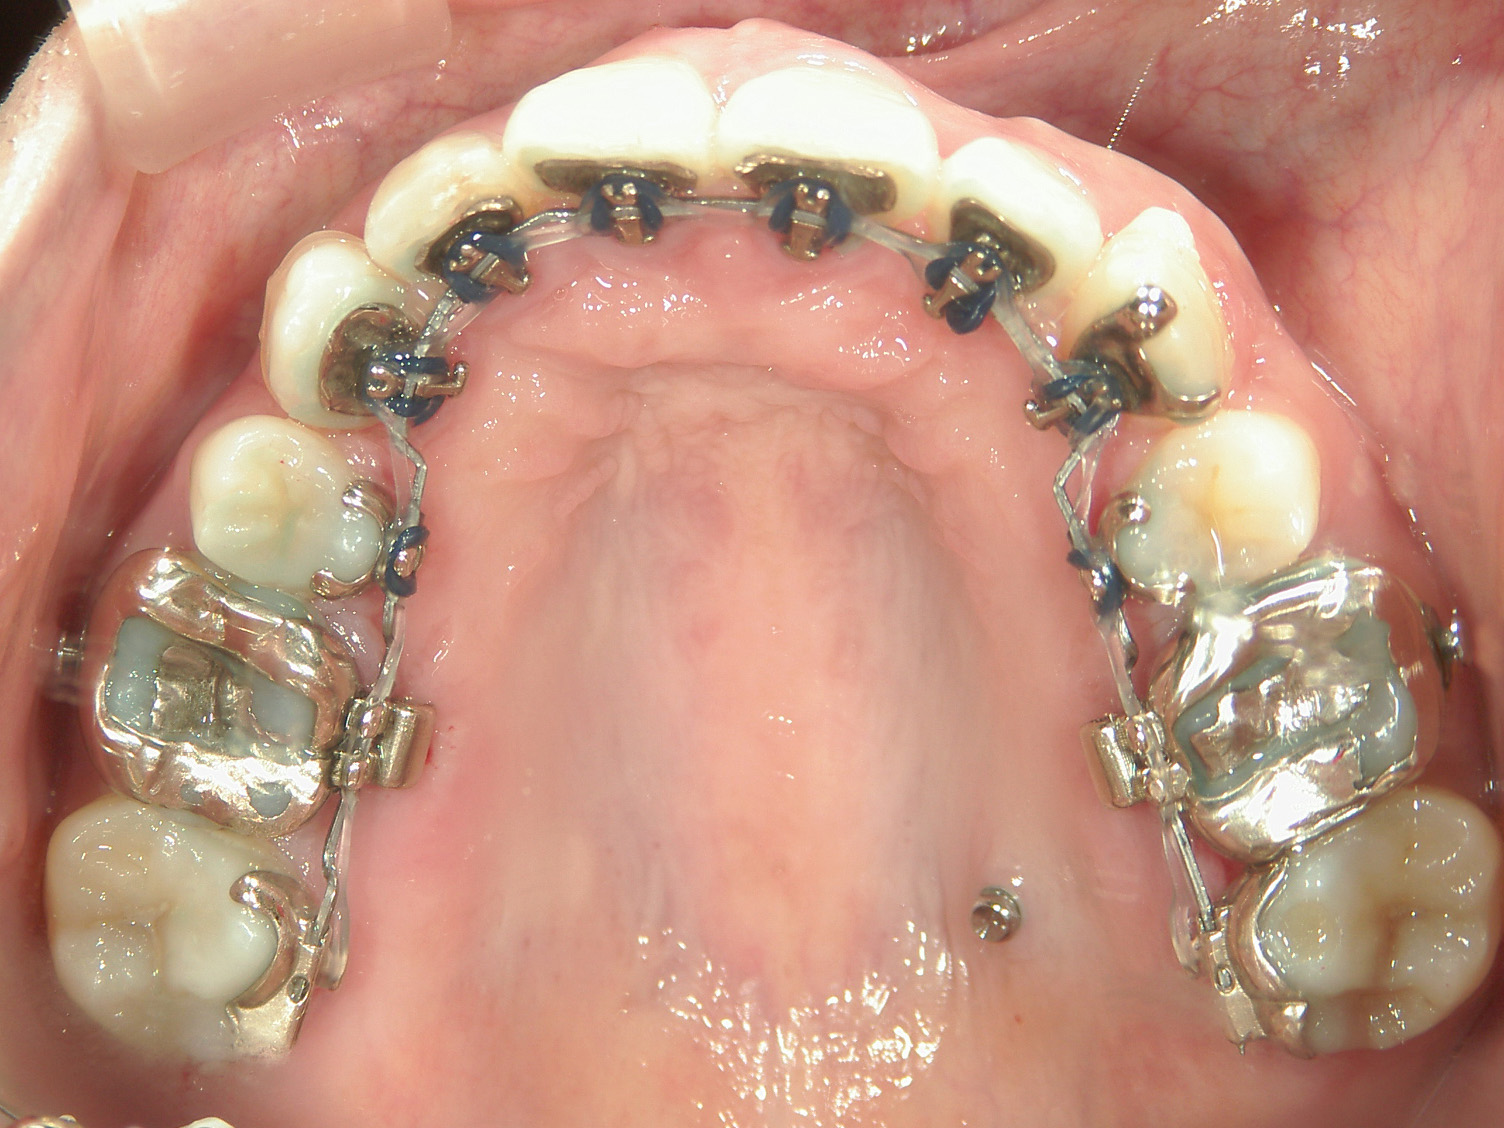

矯正装置(BH・QH)を併用。

ミニインプラント、アップライトスプリングを併用。